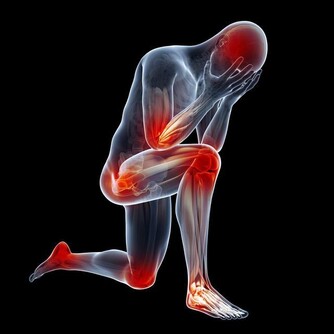

原來常常手麻是一種病!!引起手麻是這些原因.....經常手麻的朋友一定要看!

引起手麻較為常見原因的有以下幾種

手麻的常見症狀

有的人半夜手麻醒來; 有的人晨起手掌僵硬, 麻木, 過一會兒就好了.

有的人拎重物久則手麻, 手掌無力. 有的人拿碗, 一會兒就麻且無力, 不能再拿了.

有的人整天都麻. 有的人整個手掌均麻.有的人1~2 個手指麻. 手麻是一個症狀,

如果影響到日常生活, 就很不方便; 要馬上去看醫生;

如果不影響生活, 也不可以掉以輕心,它往往是一些疾病的先兆. 特別是大腦的問題.